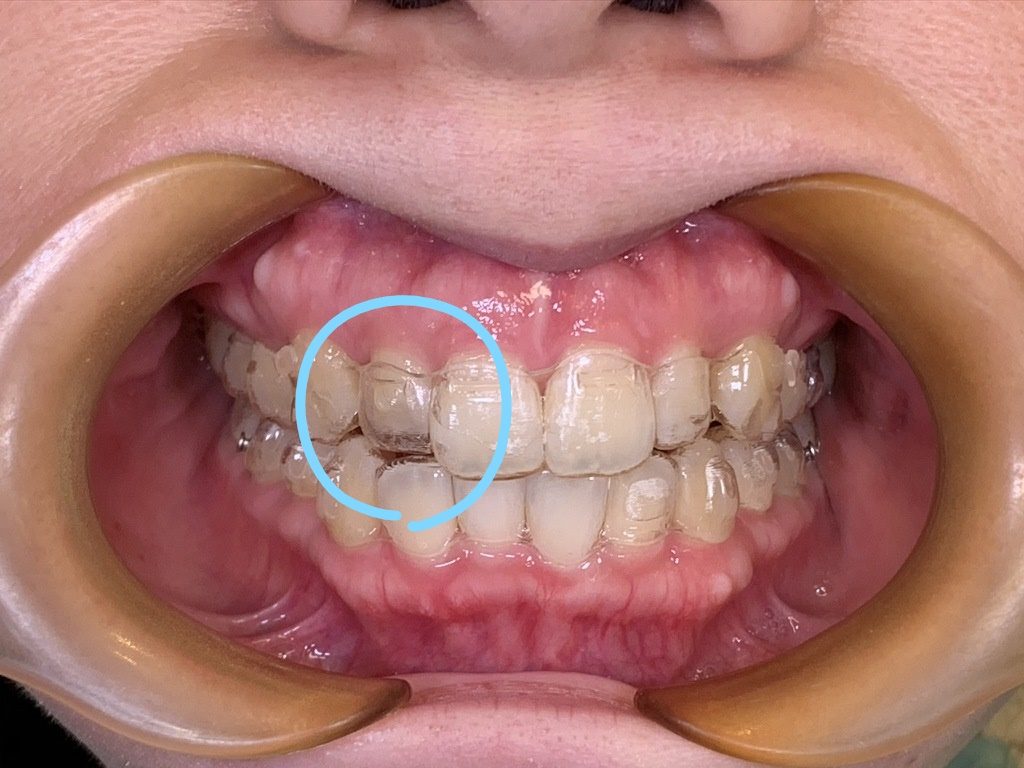

↑この〇で囲んだ部分が「浮き」です。分かりやすい画像ですが、他の部分はしっかりとはまっていても1部分でも浮きがあれば進めてはいけません!!